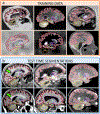

Despite advances in data augmentation and transfer learning, convolutional neural networks (CNNs) difficultly generalise to unseen domains. When segmenting brain scans, CNNs are highly sensitive to changes in resolution and contrast: even within the same MRI modality, performance can decrease across datasets. Here we introduce SynthSeg, the first segmentation CNN robust against changes in contrast and resolution. SynthSeg is trained with synthetic data sampled from a generative model conditioned on segmentations. Crucially, we adopt a domain randomisation strategy where we fully randomise the contrast and resolution of the synthetic training data. Consequently, SynthSeg can segment real scans from a wide range of target domains without retraining or fine-tuning, which enables straightforward analysis of huge amounts of heterogeneous clinical data. Because SynthSeg only requires segmentations to be trained (no images), it can learn from labels obtained by automated methods on diverse populations (e.g., ageing and diseased), thus achieving robustness to a wide range of morphological variability. We demonstrate SynthSeg on 5,000 scans of six modalities (including CT) and ten resolutions, where it exhibits unparallelled generalisation compared with supervised CNNs, state-of-the-art domain adaptation, and Bayesian segmentation. Finally, we demonstrate the generalisability of SynthSeg by applying it to cardiac MRI and CT scans.